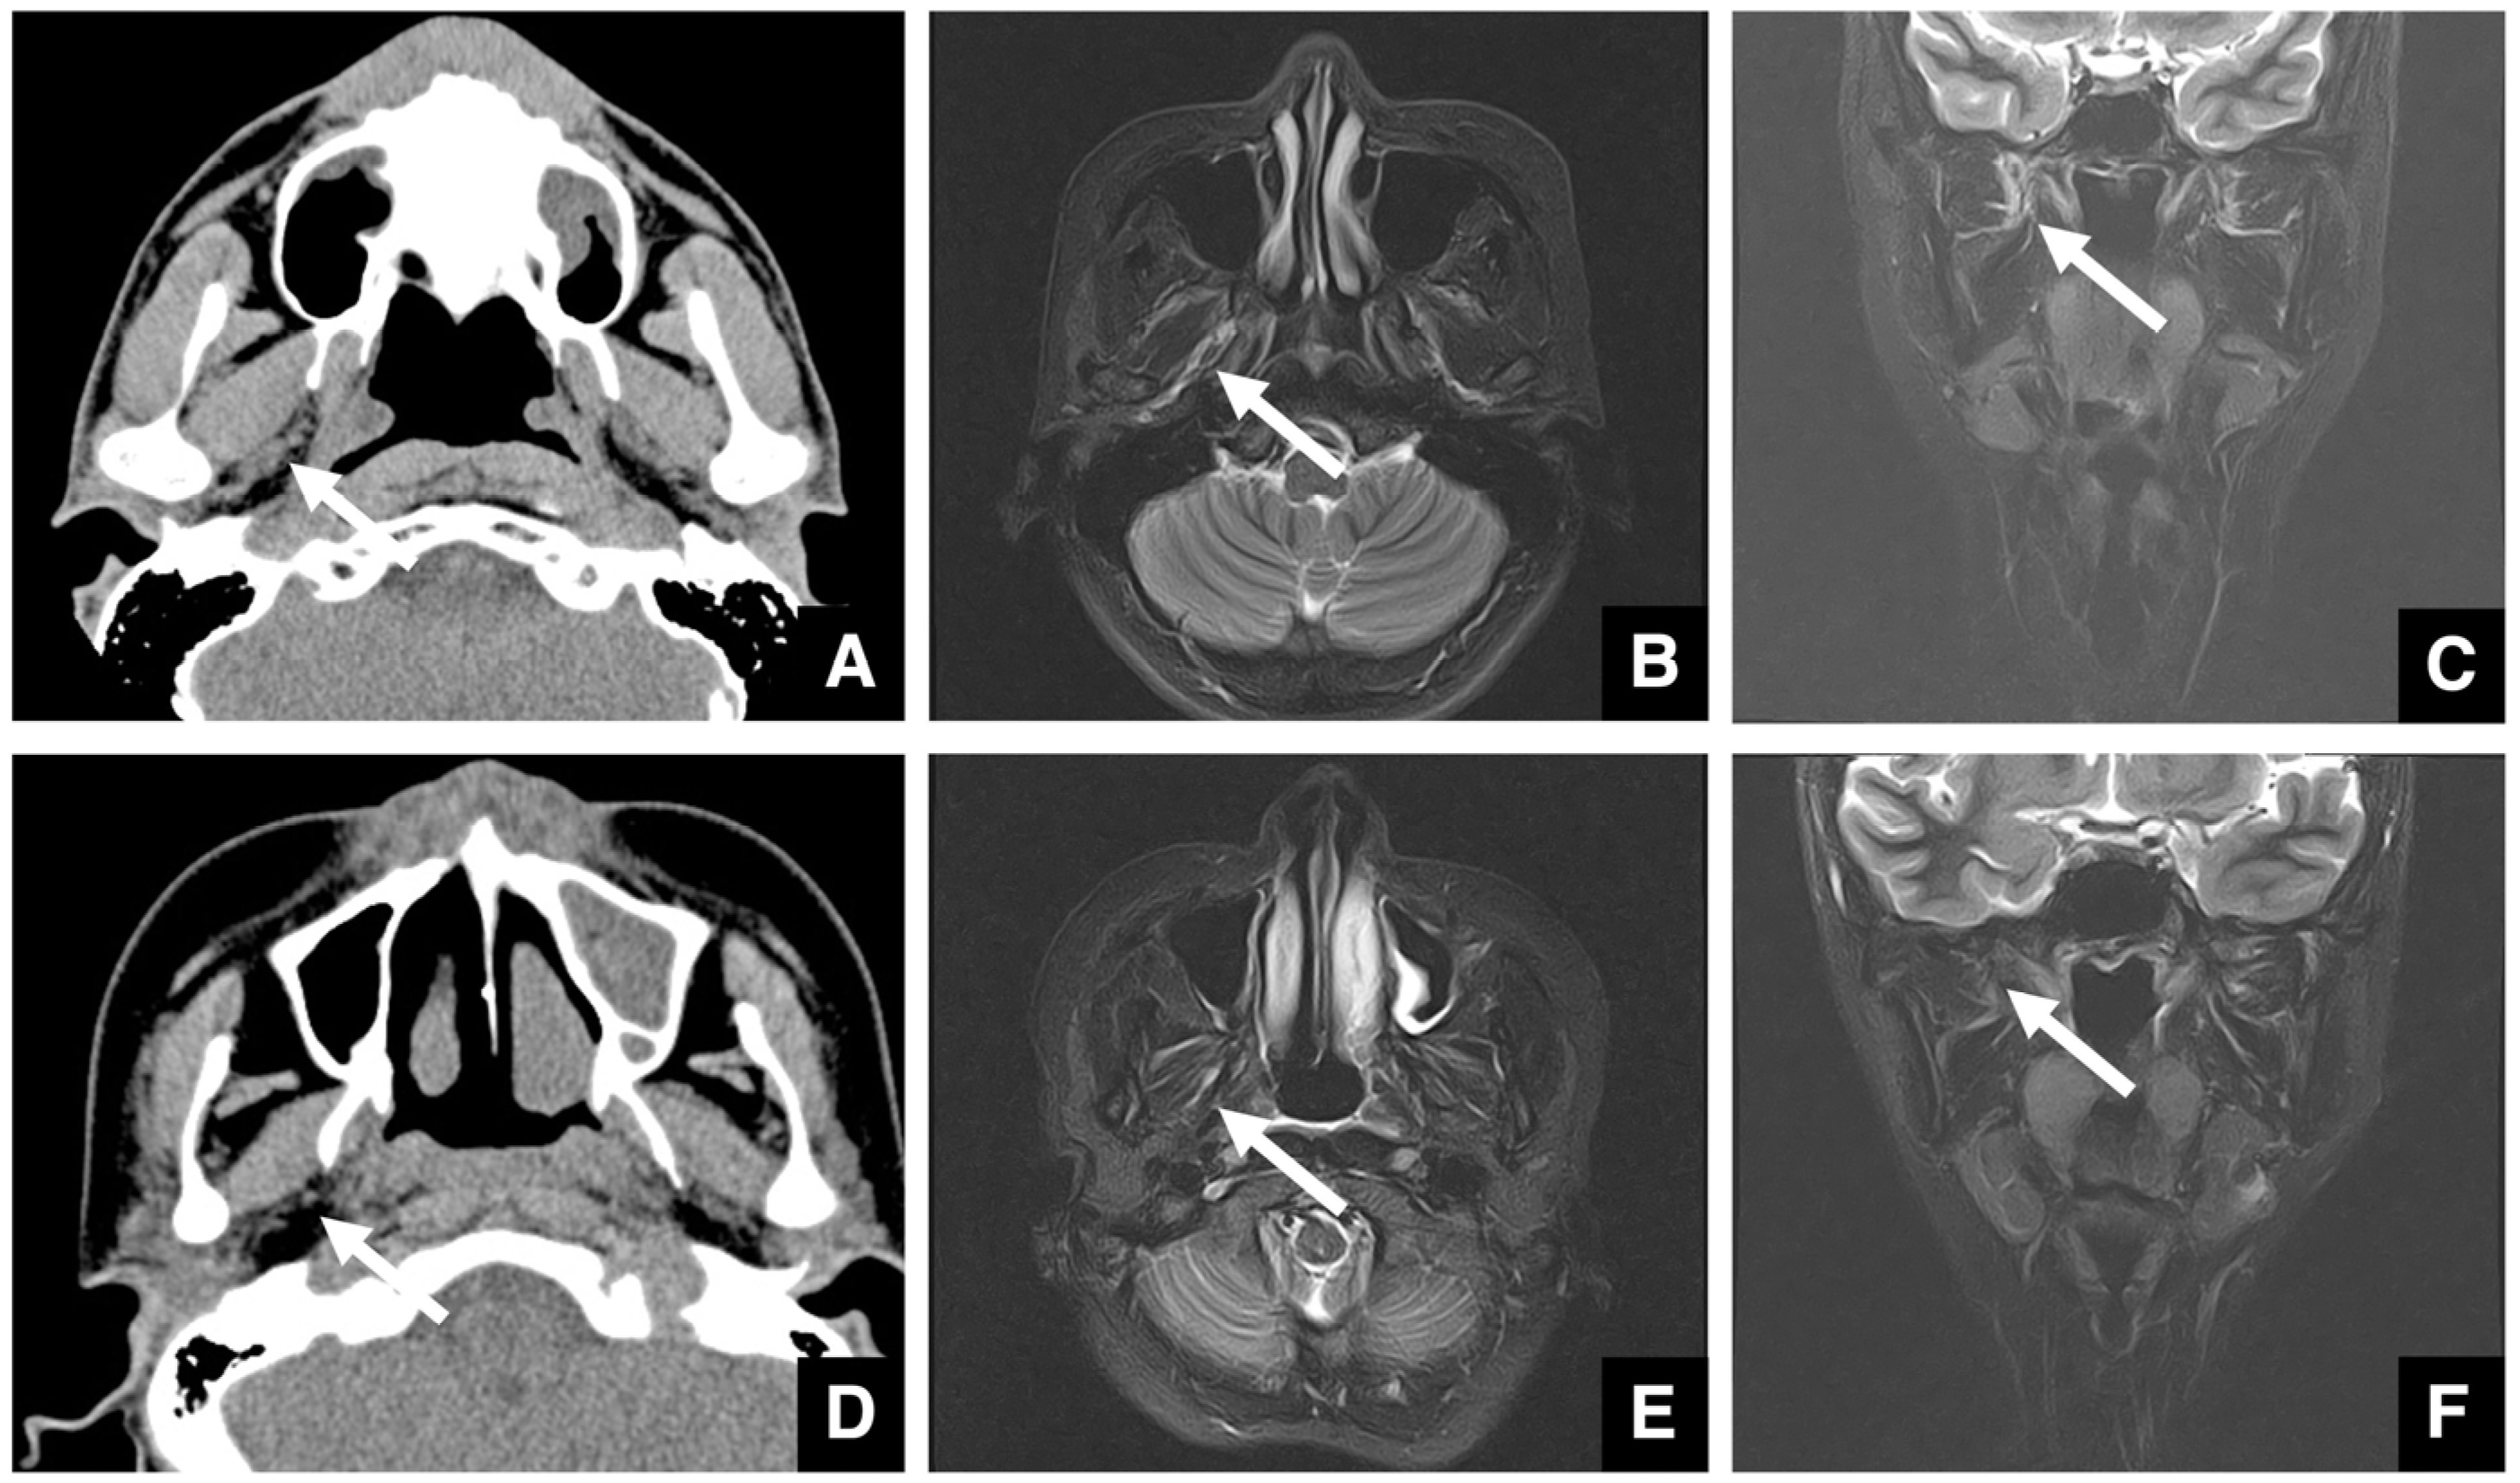

| Improving safety through prediction of surgical difficulty and complication 1. Circumstance of pterygoid venous plexus Carefully observe the fat tissue surrounding the medial and lateral pterygoid muscles to assess the development of the internal vascular structures (using CT and MR to evaluate the size of the fat tissue) 2. Fusion status of the maxillary tuberosity and pterygomaxillary suture When the fusion is narrow and the degree of calcification (CT number) is low or when the fusion is wide and high 3. Course of the descending palatine artery and thickness of surrounding bone When the palatal canal wall is thick, the probability of damage during transection is low. When it is thin, the possibility of damage cannot be ruled out. Setting the osteotomy line 1. Distance from the piriform rim to the greater palatine canal Long, short, cortical bone thickness, presence or absence of bone irregularities 2. Evaluation of the size, morphology, and internal features (mucosa, septa, etc.) of the maxillary sinus Size, shape, presence or absence of septa, presence or absence of masses, presence or absence of mucosal thickening 3. Relationship between the floor of the maxillary sinus and the apices of the molars Describe the maxillary sinus floor and the apex of each molar tooth 4. Presence of nasal septal deviation, size of the nasal passages, and thickness of the lateral nasal wall bone Presence or absence of nasal septal deviation, Size of the nasal passage, Thickness of the cortical bone of the lateral wall 5. Course of the mandibular artery The course from the pterygoid cleft to the pterygopalatine fossa in the posterior maxilla |